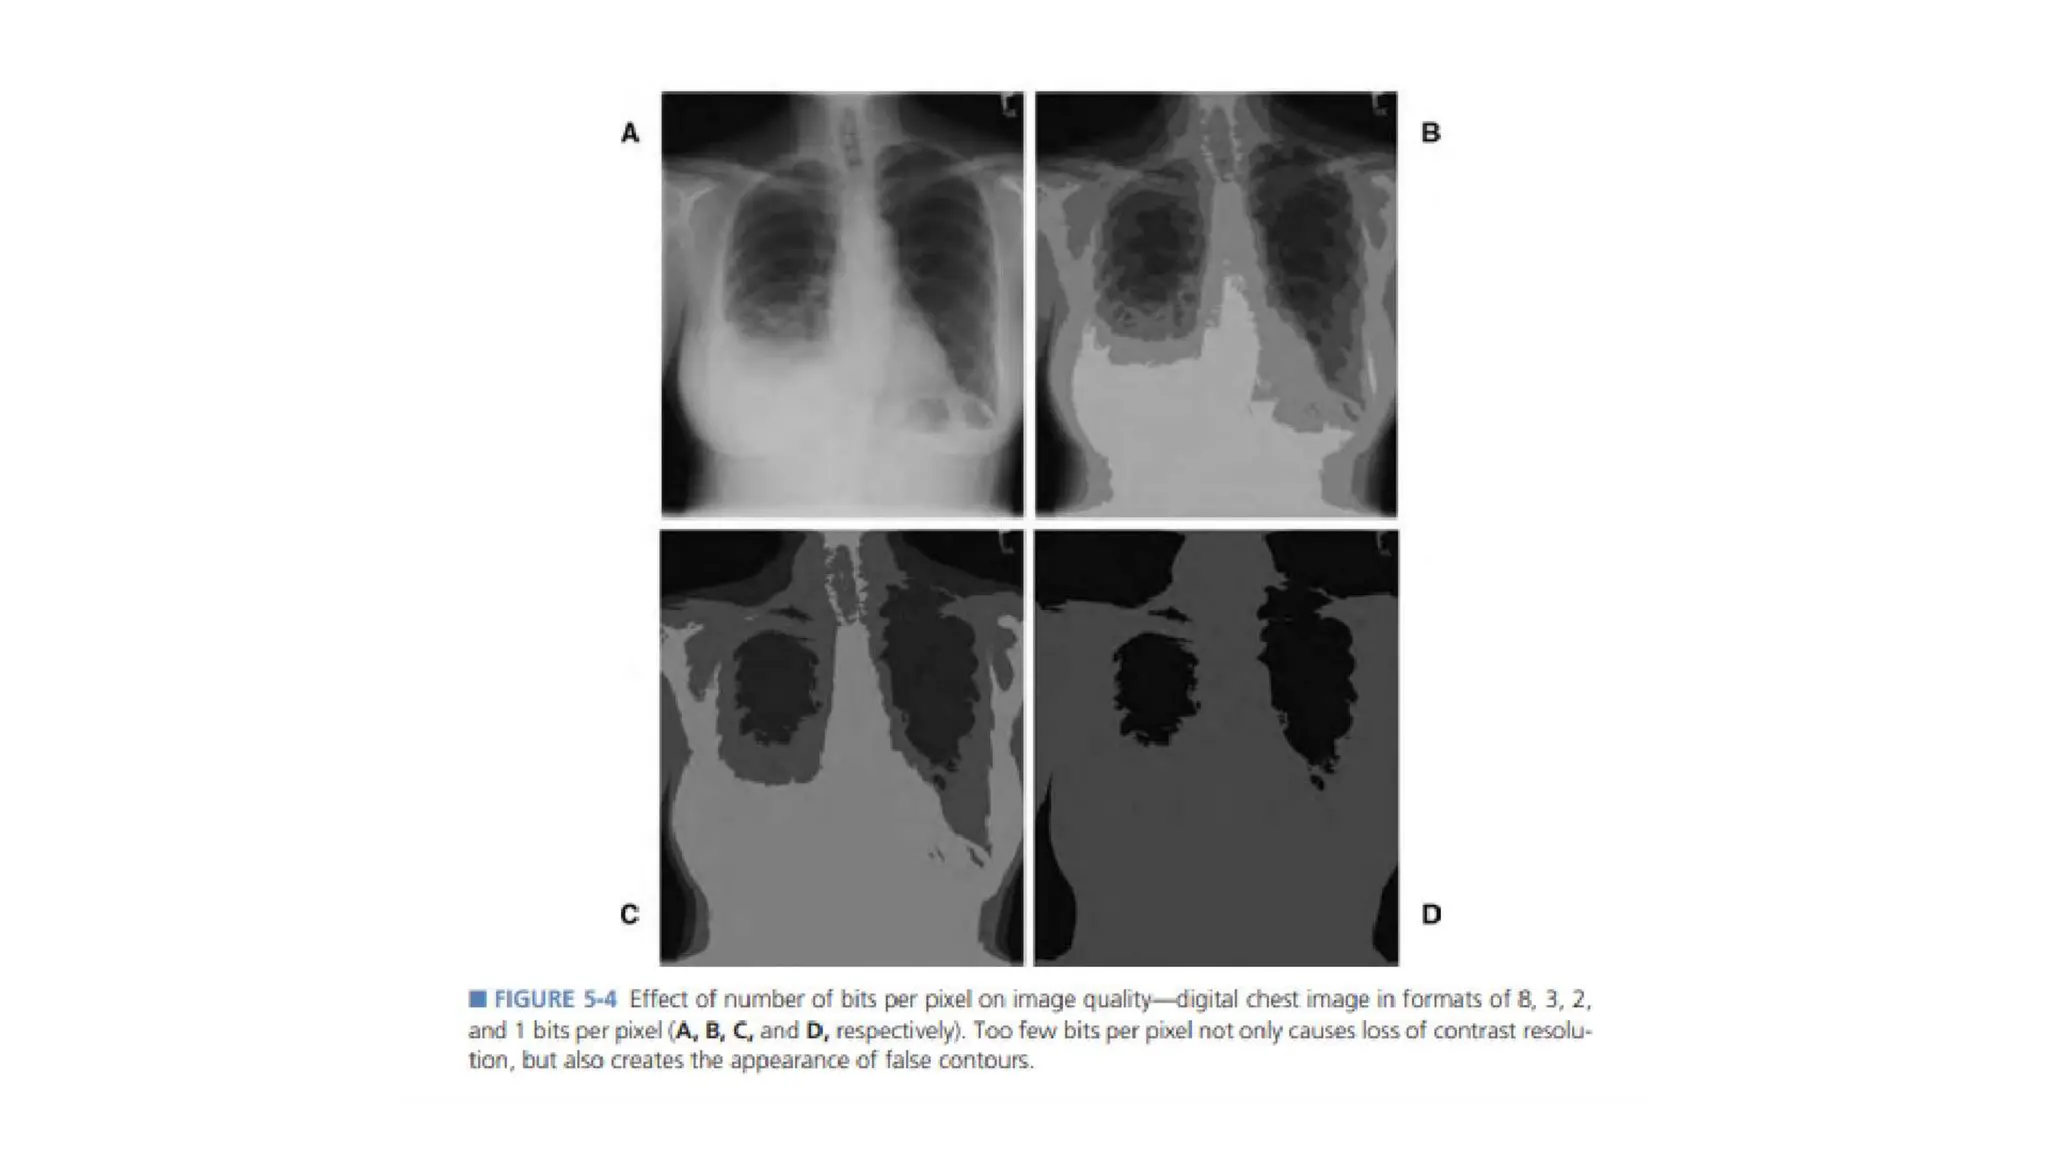

Pixel Bit depth

• The pixel bit depth is the number of bits that indicates the different

shade of the gray used to define each pixel.

• A one bit (2^1) image can display only 2 shades of gray i.e. black &

white & such an image will display very little or no more information.

• Most digital image use a dynamic range of 8,10 or 12 bit meaning a

gray scale range 2^8 , 2^10 , or 2^12.

• Higher bit depths generally result in better color fidelity and image

quality with better contrast resolution.